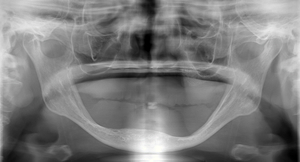

何年も義歯に問題を抱えて来院された方

大きく骨が吸収しています。これ以上吸収すれば、骨折の危険性もあります。